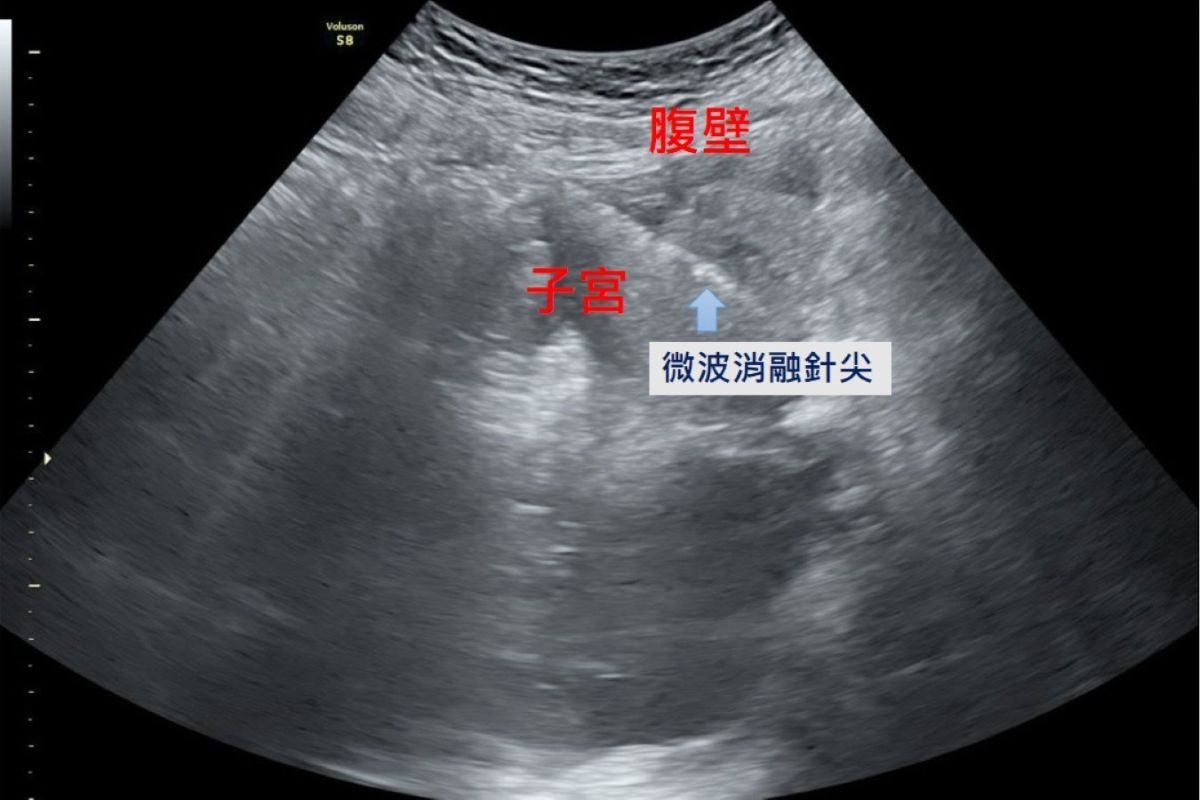

臨床診斷子宮肌腺瘤可以透過病人主訴、內診、超音波及抽血檢查來判斷。過去的治療方式有藥物及手術摘除子宮兩種,藥物治療可暫時控制經痛與經血過多,但長期使用荷爾蒙類藥物抑制劑容易出現類似停經更年期的副作用,例如熱潮紅、盜汗與骨質疏鬆;手術切除全部子宮雖能徹底移除病灶,但對希望保留子宮或仍有生育計畫的女性而言就無法再生育,代價較大;而若只切除局部子宮肌腺瘤,則無法完全清除、症狀改善有限。隨著醫療科技的進步,微波消融成為近年來的治療新選擇,醫師在腹腔鏡及婦科超音波的導引下,將消融針精準進入病灶,釋放高能量微波破壞異常內膜腺體組織,使其失去活性而逐漸縮小壞死,達到止痛與減少經血的治療目的。陳國瑚部長表示:「微波消融治療的範圍可透過影像導引精準掌握,不容易傷害周邊組織,也因為術中保護子宮內膜,病人術後不影響懷孕。此外,微波消融治療術後疼痛感低、併發症風險也較小,根據臨床追蹤,近九成的病人預後狀況良好,能恢復正常月經週期,經痛大為改善,提升生活品質。」